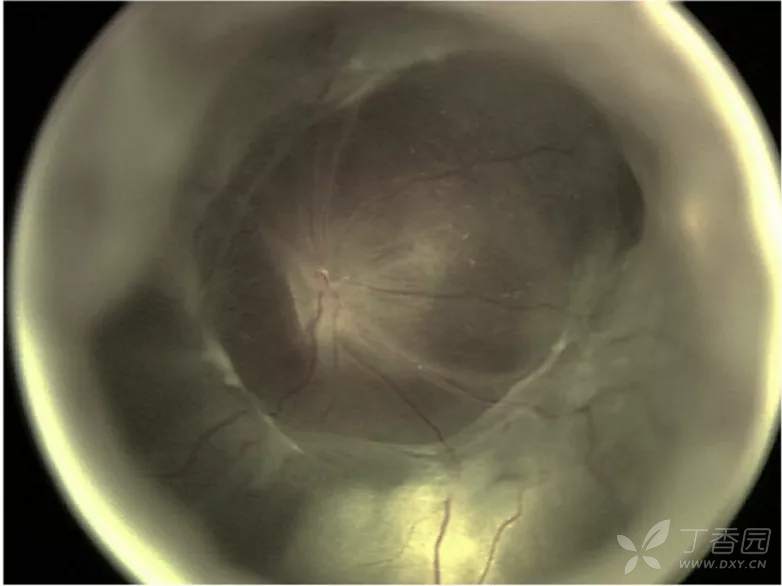

07、急性早产儿视网膜病变5期:完全视网膜脱离

图. 5A期:视网膜完全脱离并可见视盘,提示开放漏斗型脱离。